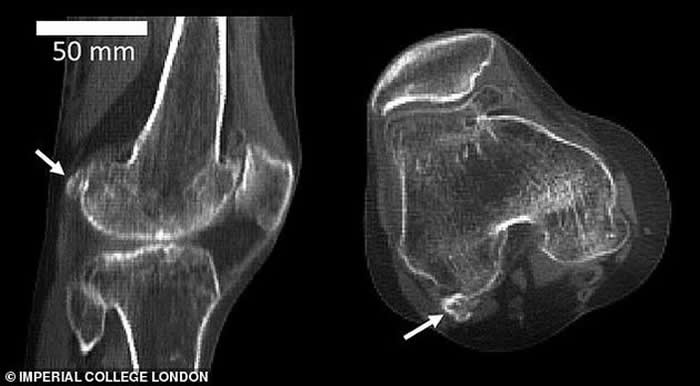

豆骨(fabella),是位于膝盖后方肌腱中的一块小骨骼,目前它在人体存在的概率是100年前的3倍,全球五分之二居民都长有豆骨。

豆骨(fabella),是位于膝盖后方肌腱中的一块小骨骼,目前它在人体存在的概率是100年前的3倍,全球五分之二居民都长有豆骨。它的直径不足1.3厘米,是在我们灵长类祖先身体上发现的,它被称为“骨骼阑尾”,因为它的存在是毫无意义的。

英国伦敦帝国理工学院的研究人员回顾了过去150多年进行的2.1万多项科学研究,其中包括研究人员扫描和解剖鉴定发现豆骨的存在。他们从中发现1918年全球11.2%居民体内存在豆骨,但依据发表在《解剖学杂志》的这篇评论报告,截至2018年,全球39%居民体内存在豆骨。

伯托姆博士称,当远古灵长目动物进化成大猿和人类,我们似乎已不再需要豆骨,现在它只会给我们带来麻烦,但有趣的是,近年来人体出现豆骨的概率骤增。这项最新研究发表在《解剖学杂志》上,作者详细研究了25个国家21676个膝盖数据,最早的数据可追溯至1875年。这些膝盖数据来自多种渠道,其中包括:X射线、核磁共振扫描和局部解剖。